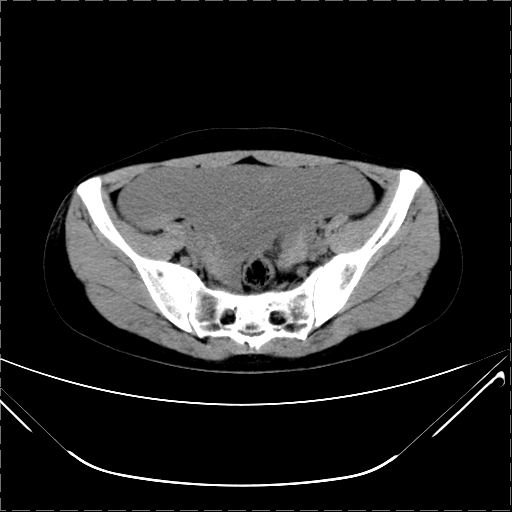

女 29岁 突然腹部疼痛1天 b超示子宫左后方肿块。月经正常。

影像表现复杂,膀胱上见一囊性包块,比膀胱密度高,其内有不均匀稍高密度,似与道格拉斯窝肿物无分界,病灶没有张力,因其腹平坦,推定其具有流动性,但又似见包膜,而b超没有报告这一现象。确实没见过。考虑卵巢囊肿蒂扭转并囊内出血可能。

那要好好查查出血的原因.影像表现主要是盆腔积血的改变

病变主要位于道格拉斯窝,而且大体形态比较扁平且贴合子宫直肠,无明显张力及对周围脏器压迫,所以考虑为液体,而中间可见囊样病变伴环形强化,期内还可见分隔影,结合突发急性腹痛故多考虑囊腺瘤伴破裂出血。

腹腔镜术后 卵巢黄体囊肿破裂出血